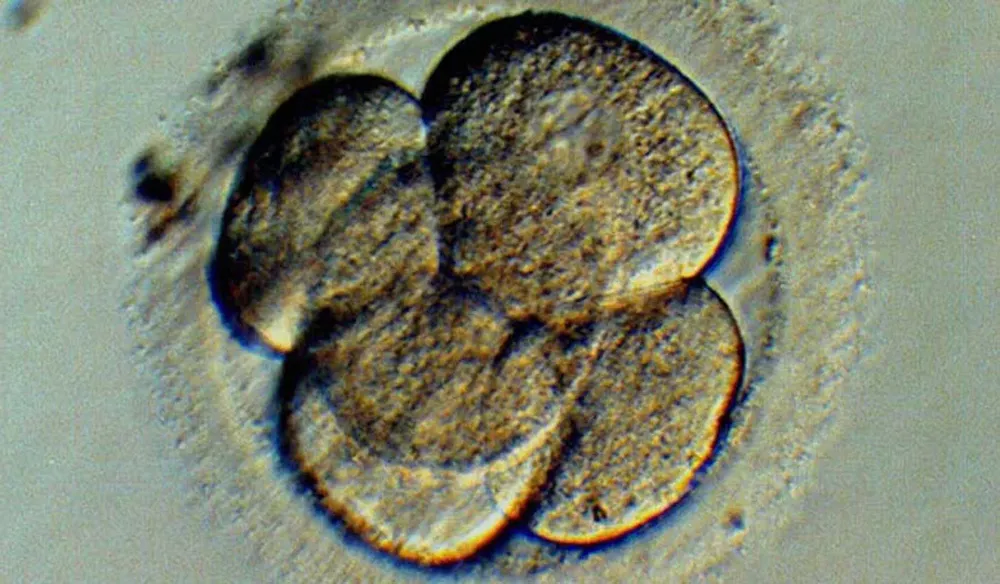

Según datos en poder del MSP, en Uruguay se hacen unas 600 fertilizaciones in vitro por año, con un costo promedio de US$ 6.000 cada una (aunque cuando tiene especificaciones llega a valer US$ 12 mil). Algunas mujeres pueden hacerse más de una fertilización. La experiencia internacional indica que cuando estas técnicas dejan de ser costodependientes, la demanda se triplica. Esto significa que habrá como mínimo 1.800 solicitudes de fertilización in vitro por año cuando empiece a regir la ley. Pero en el MSP saben que también hay que tener en cuenta a las uruguayas que viajan a Buenos Aires porque allí la medicación es más barata. No saben con certeza cuántas son, pero estiman en unas 200.

In vitro. En Uruguay se realizan unas 600 fecundaciones in vitro anuales. El MSP estima que unas 200 uruguayas viajan a Argentina a hacerse el tratamiento porque la medicación es más barata.

Mínimo. Según la experiencia internacional, cuando la prestación deja de ser costodependiente, se triplica la demanda. Significa que a partir de marzo habrá al menos 1.800 fertilizaciones por año.

Millones. El costo de que 1.800 parejas se hagan una fertilización in vitro asciende a US$ 11 millones, si se considera que, en promedio, el tratamiento cuesta US$ 6.000. Según la ley, la financiación de estas técnicas dependerá del Fondo Nacional de Recursos.